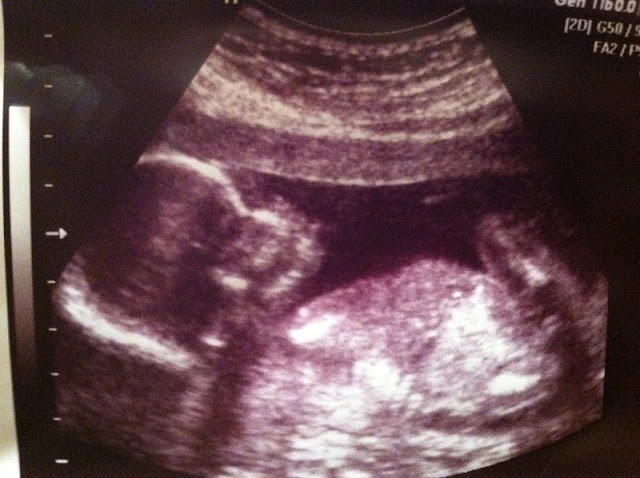

Well I am almost 19 weeks now, but here is my 18 weeks post. ITS A GIRL!!!! I saw it right away, but the tech didn't confirm it to us until about 5 minutes into the ultrasound. I think she was wanting to add to the suspense. I had tears running down my face, of happiness of course. I can't wait to see what she looks like. Will she have my strawberry blonde hair and blues eyes or will she look just like her brother. Emma Grace, I can't wait to meet you!

Looking forward to: Seeing Emma at my 20 week ultrasound (actually scheduled at 21 weeks). Ethan asks everytime we go to the drs if we are going to see the baby on the TV. So cute!